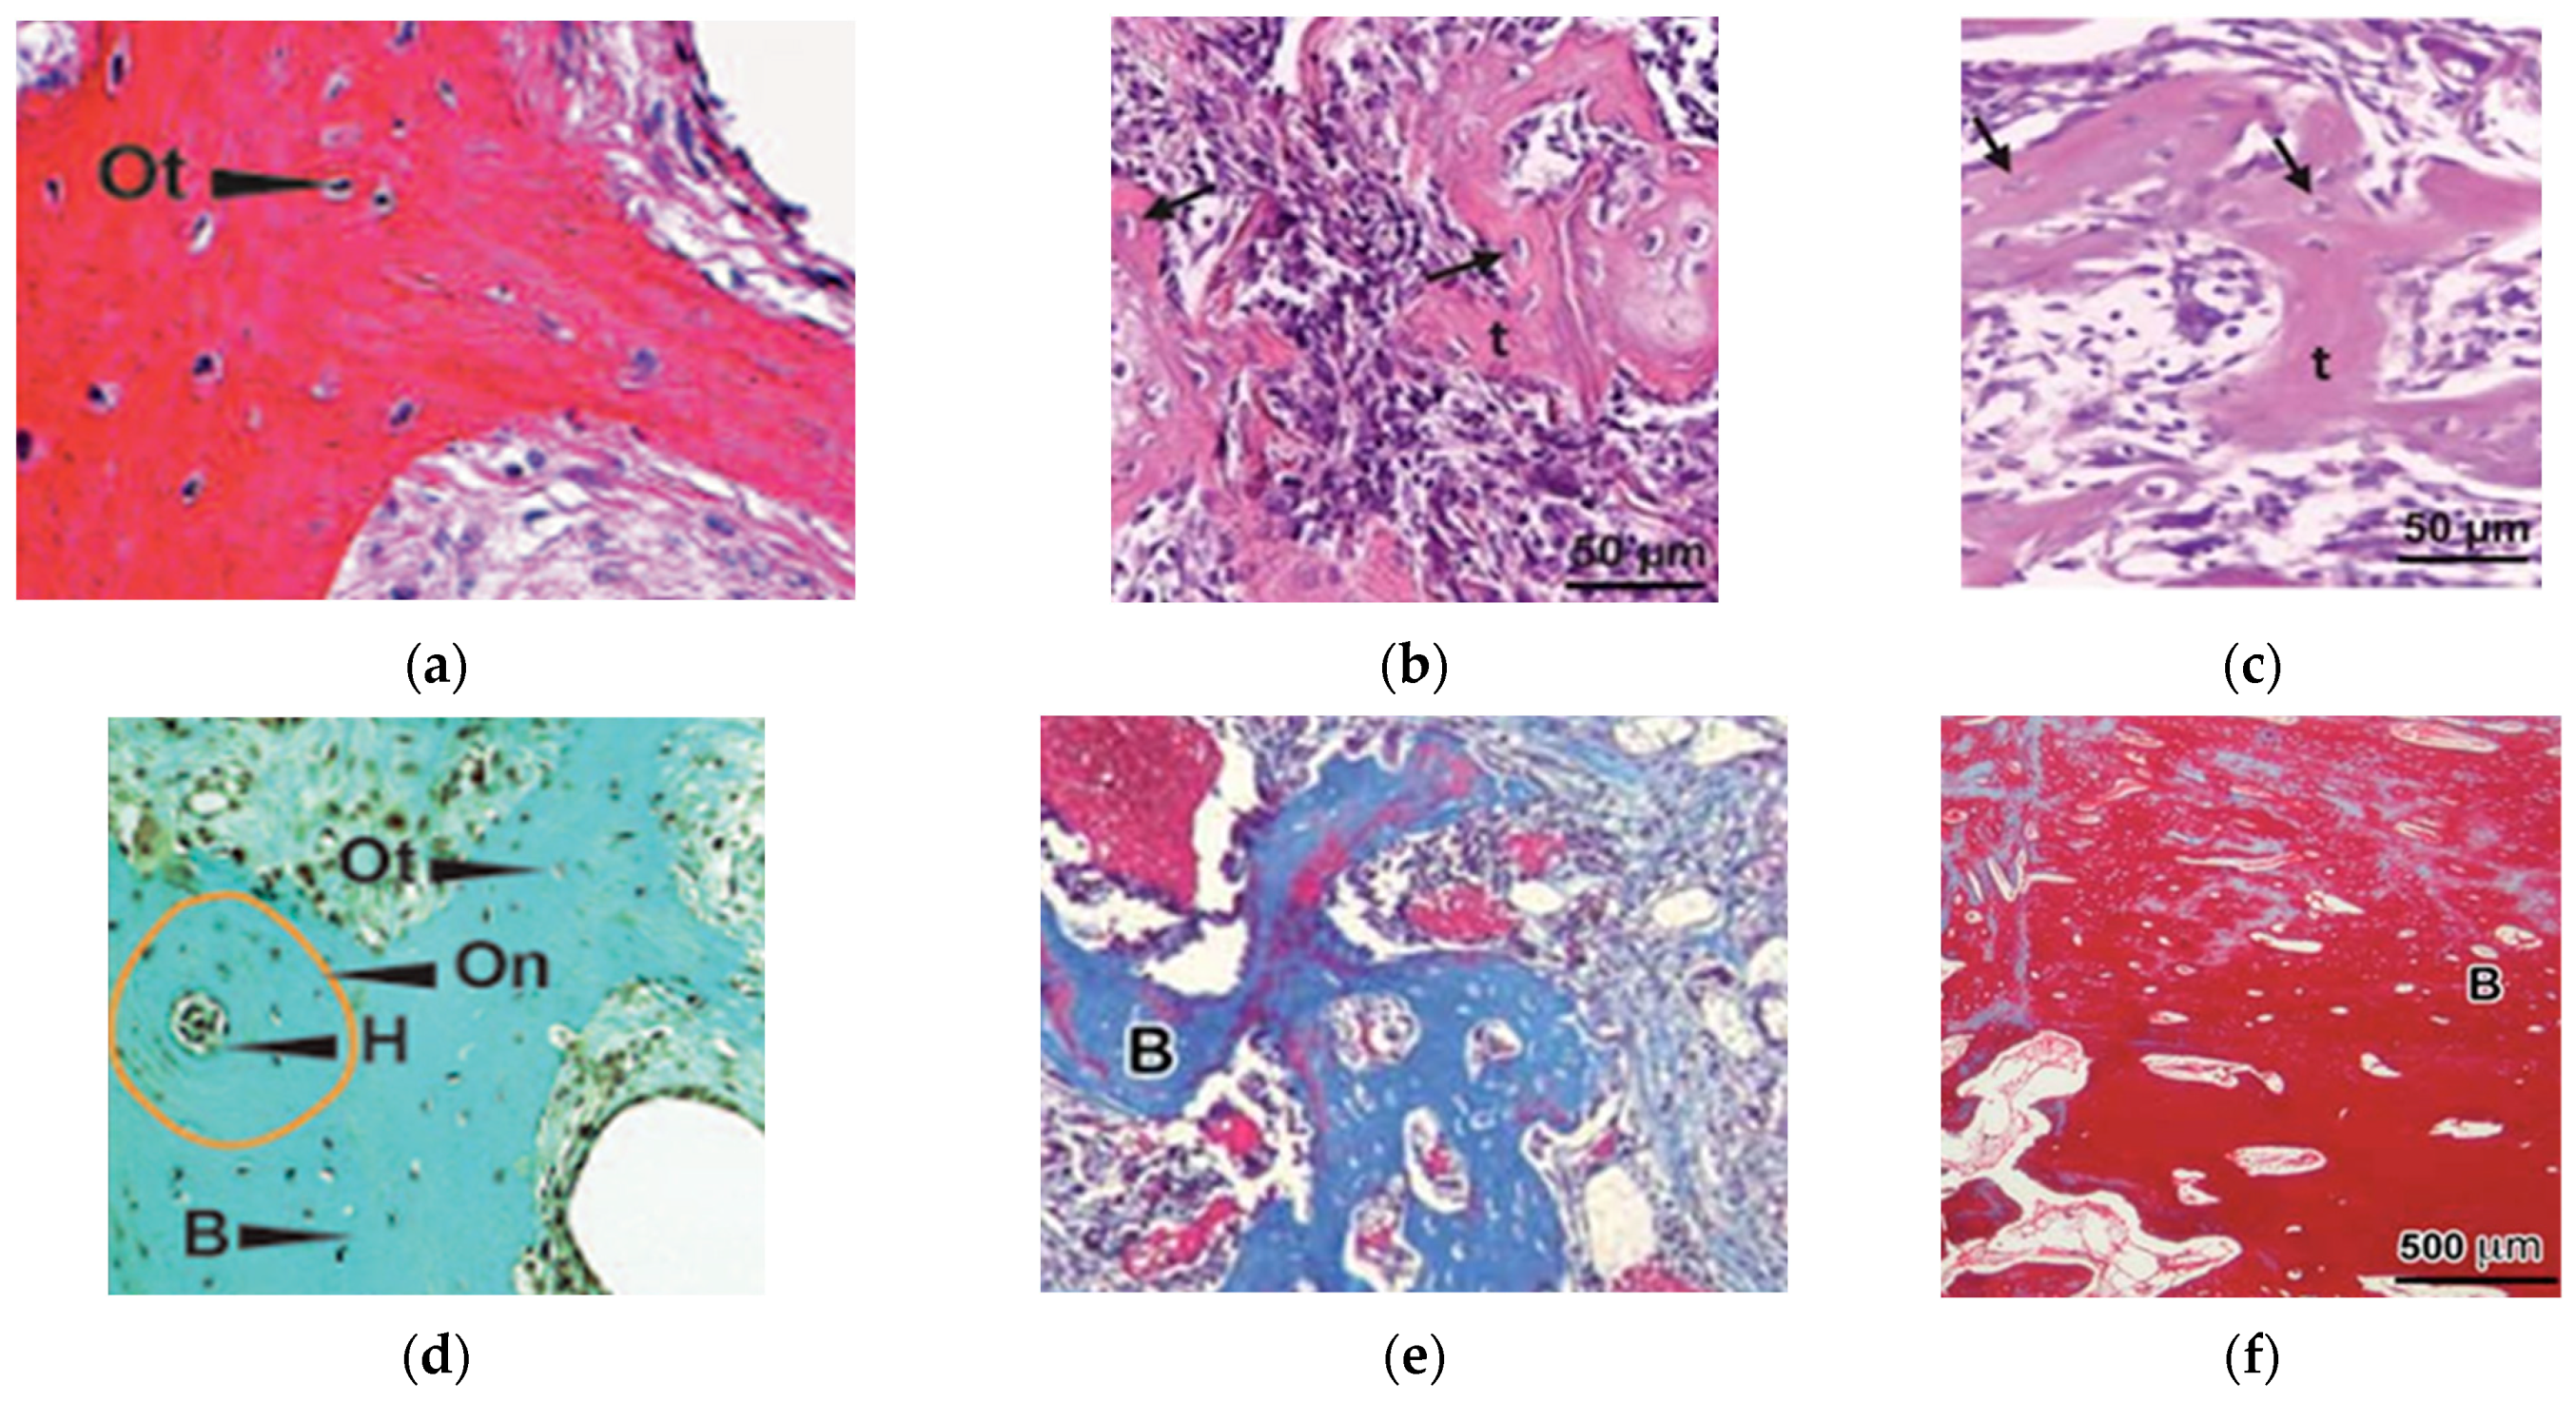

3.2.1. Histologic Evaluation

3.2.2. Radiologic Evaluation